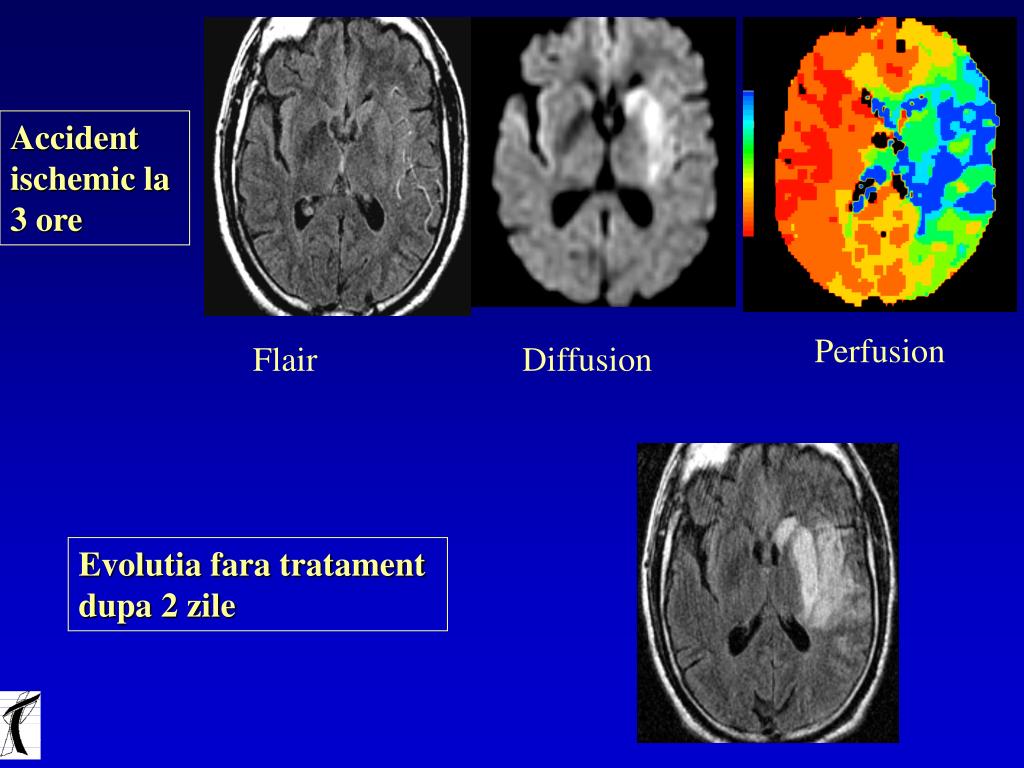

6. Accident ischemic la 3 ore Perfusion Flair Diffusion Evolutia fara tratament dupa 2 zile